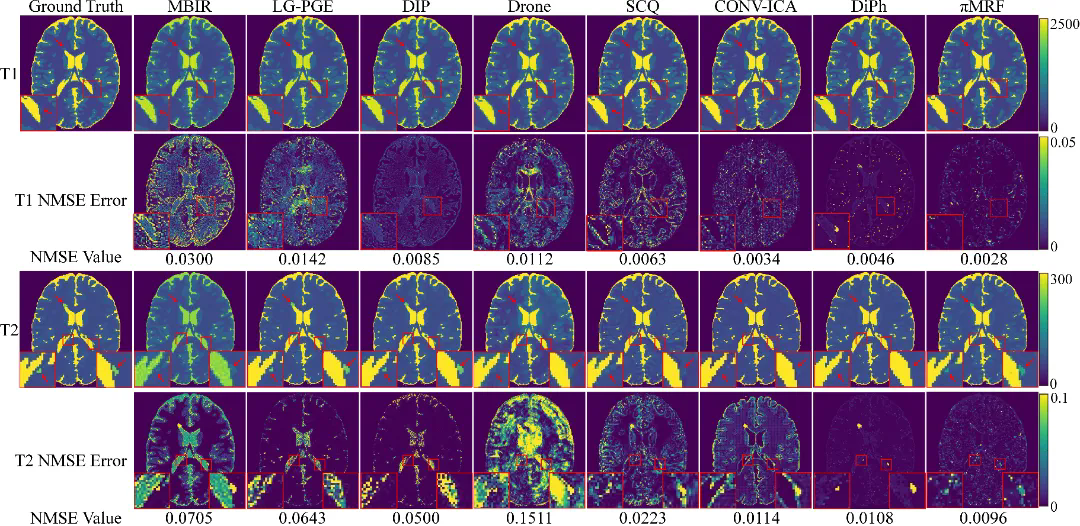

在数字仿真、水模仿体以及在体人脑实验中,πMRF在极端欠采样条件下均表现出更高的定量准确性与空间一致性,能够稳定恢复T1、T2和PD参数分布,并在组织边界及病灶区域保持更可靠的细节表达,整体性能显著优于现有对比方法。上述结果表明,该研究有效缓解了 MRF 在极端欠采样条件下面临的不适定逆问题,展示了“物理模型与连续神经表示深度融合”在复杂医学成像反演任务中的应用潜力。

图3:数字仿真实验结果